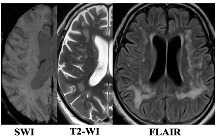

2.2. Expression of Inflammation-Associated Genes: CSVD Group vs. Control and MRI Types 1 and 2 CSVD vs. Control